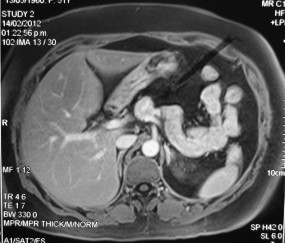

Se sometió a la paciente a cirugía abierta; se practicó una incisión mediana supraumbilical, lo que permitió aperturar la transcavidad de los epiplones (Figura 2). Se pudo observar directamente la lesión, por lo que no fue necesario contar con otras imágenes intraoperatorias. Se procedió a realizar la palpación bimanual del páncreas, por lo cual se realizó la maniobra de Kocher extendida para evaluar la profundidad de la lesión.

Figura 2 Lesión nodular de aproximadamente 2 cm